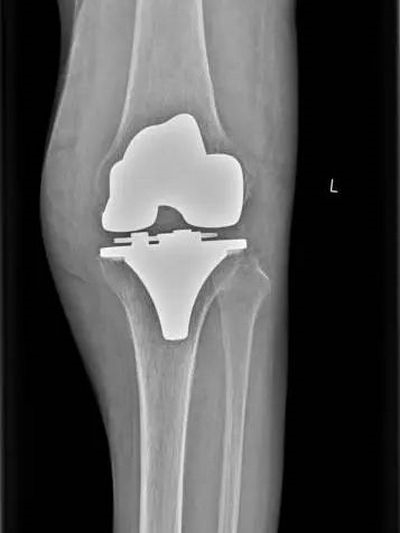

术后检查

术后践行ERAS快速康复理念,指导患者屈伸活动膝关节,并结合我院康复的优势,对患者床旁进行康复锻炼,术后第3天患者膝关节即可屈曲90°,王奶奶每次见到医师都赞不绝口。

徐明杰主任说到,膝关节表面置换术是指使用膝关节置换器械,做股骨髁、胫骨平台截骨,去除磨损的软骨和多余的骨赘,用钛或钴铬钼合金和高分子聚乙烯进行关节表面置换。